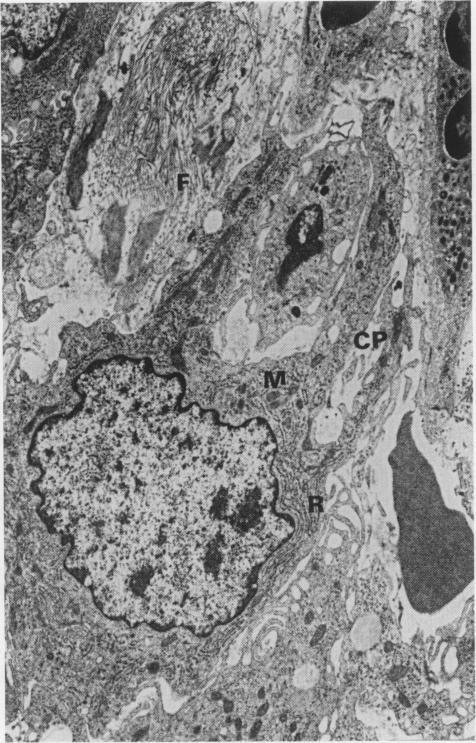

The herbicide paraquat induces irreversible progressive pulmonary fibrosis in human beings and animals. The mechanisms of the fibrosis are still unresolved. There is histological and ultrastructural evidence that an early destructive phase followed by a proliferative phase occurs in the lungs post paraquat-exposure. In this study, lungs obtained from a dog 7 days following intravenous administration of paraquat (12 mg paraquat dichloride per kg bodyweight) are compared with lungs obtained from a normal dog. Examination included gross post mortem inspection, histology, transmission electron microscopy (TEM) and scanning electron microscopy (SEM). Comparison of the TEM of the paraquat affected canine lung with the normal showed: alveolar collapse; detachment of alveolar epithelial cells from the basement membrane; alteration of the type II alveolar cell morphology; infiltration of granulocytes and erythrocytes into both the interstitium and alveolar air spaces; and fibroblasts associated with collagen fibrils. The SEM of the paraquat-exposed canine lung, reported here for the first time, demonstrated irregular, alveolar walls with type I alveolar epithelial cell detachment, and erythrocyte and alveolar macrophage infiltration. These findings suggest that the detachment of alveolar epithelial cells and the alveolar macrophage play a significant role in paraquat-induced pulmonary fibrosis.

除草剂百草枯可在人和动物中诱发不可逆的进行性肺纤维化。纤维化的机制仍未明确。有组织学和超微结构证据表明,百草枯暴露后肺内会出现一个早期破坏阶段,随后是增殖阶段。在本研究中,将静脉注射百草枯(每千克体重12毫克二氯化百草枯)7天后的狗的肺与正常狗的肺进行比较。检查包括大体尸检、组织学、透射电子显微镜(TEM)和扫描电子显微镜(SEM)。将百草枯中毒犬肺的TEM与正常肺进行比较显示:肺泡塌陷;肺泡上皮细胞与基底膜分离;II型肺泡细胞形态改变;粒细胞和红细胞浸润到间质和肺泡腔;以及与胶原纤维相关的成纤维细胞。本文首次报道的百草枯暴露犬肺的SEM显示,肺泡壁不规则,I型肺泡上皮细胞脱落,红细胞和肺泡巨噬细胞浸润。这些发现表明,肺泡上皮细胞和肺泡巨噬细胞的脱落在百草枯诱导的肺纤维化中起重要作用。